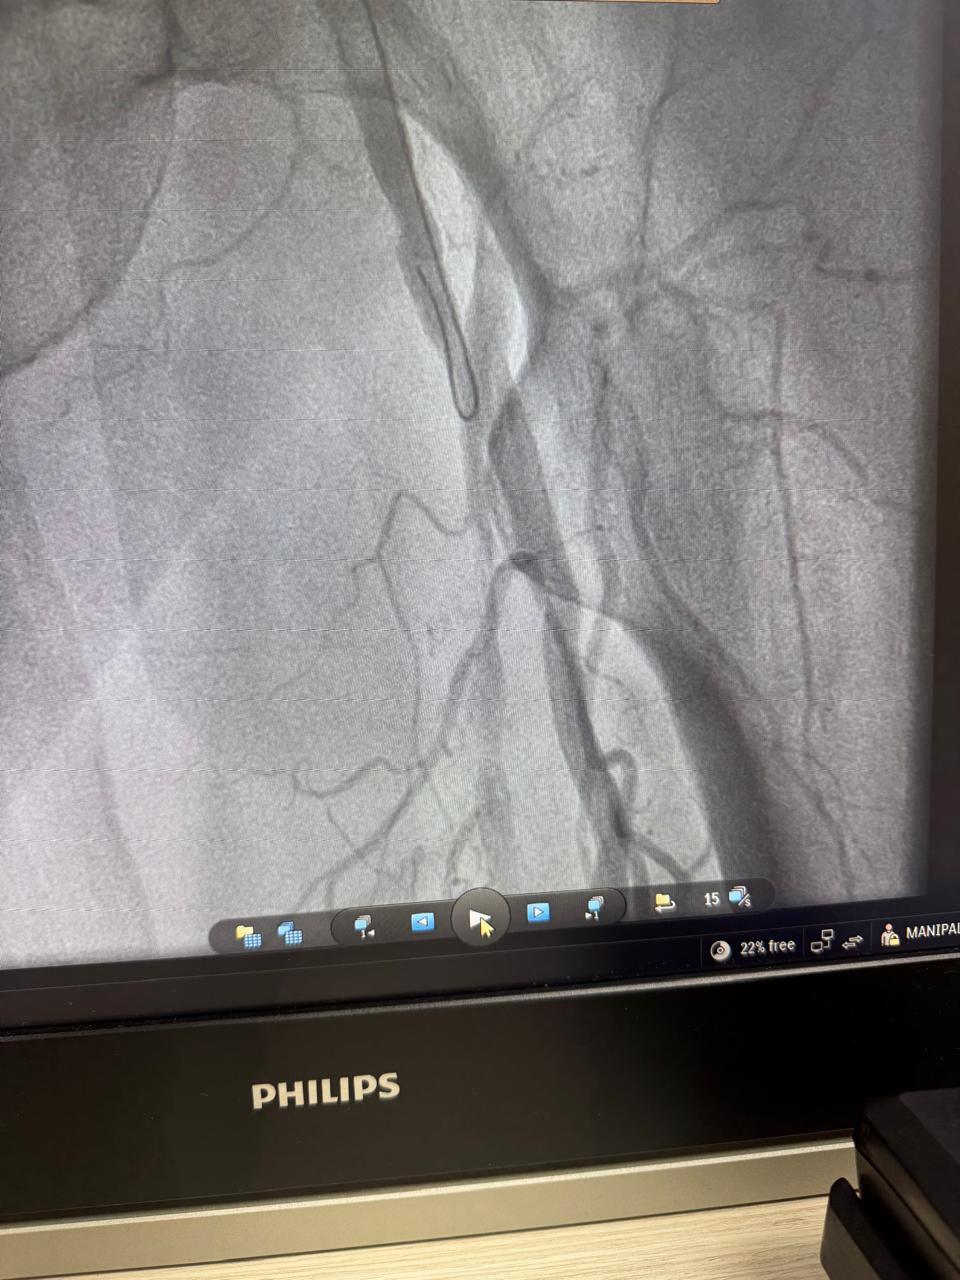

Angioembolization of traumatic right internal iliac artery ( posterior branch)injuries